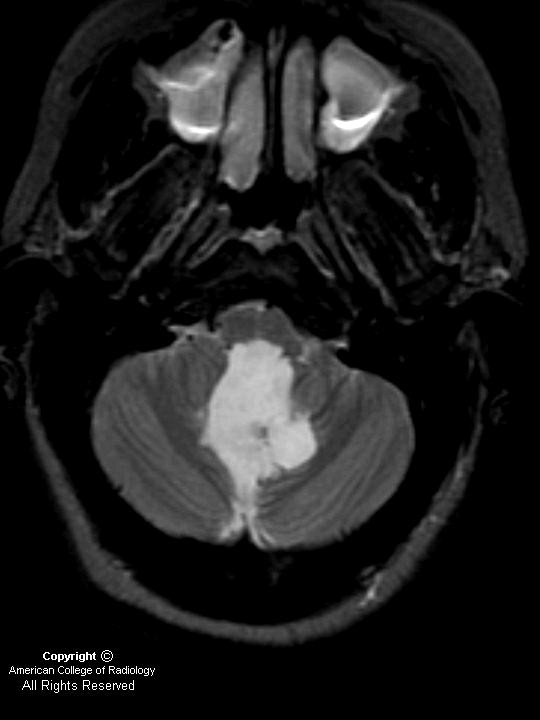

Epidermoid

Figure 1 (T1 axial) and Figure 2 (T1 post-gadolinium contrast): Lesion is slightly hyperintense to but near CSF intensity. It arises inferior to the fourth ventricle with mass effect on the adjacent cerebellum and brainstem and encroaches on the foramen magnum. Post-contrast imaging of the mass demonstrates no appreciable enhancement.

Figure 3 (T2 axial): The lesion is hyperintense on T2-weighted imaging and is of CSF intensity.

Figure 4 and Figure 5 (FLAIR): The lesion shows some mixed signal on FLAIR imaging.

Figure 6 The lesion demonstrates restricted diffusion on diffusion-weighted imaging.

Diagnosis: Epidermoid

Epidermoids compose approximately 0.2%-1.8% of all intracranial tumors. Epidermoid is a congenital CSF-like mass that is also known as a congenital epidermal inclusion cyst. This mass of epithelium arises from inclusion of ectodermal rest cells during neural tube closure at the third to fifth week of embryogenesis. They are slow-growing, well-circumscribed, smooth or lobulated lesions. Histologically, they have an internal layer of stratified squamous epithelium with a whitish fibrous capsule; given these features, epidermoids are often called a pearly tumor. Keratin and cholesterol crystals are identified within them.

Epidermoids grow slowly, and do not present until ages 20-60, peak age 40, in men and women equally. They typically present with headache or neuropathy (cranial nerves V, VII, VIII most commonly involved), and symptoms depend upon location. Most present in an intradural location, and almost half present in the cerebellopontine angle (40%-50%). Epidermoids are the third most common cerebellopontine angle mass after vestibular schwannoma and meningioma. As in this case, epidermoids may present around the fourth ventricle (17%). They may also present in the parasellar/middle cranial fossa (10%-15%), and 10% may present in an extradural location within the skull or spine.

On CT, epidermoids are typically low density and expand to fill the CSF space, insinuating around normal brain structures and appearing similar to arachnoid cysts. Epidermoids demonstrate variable appearance on T1-weighted imaging, based upon protein and lipid content, and they do not enhance after contrast administration.

Since epidermoids, like arachnoid cysts, may be similar to CSF signal on T1- and T2-weighted imaging, diffusion imaging is useful to differentiate these entities. Since arachnoid cyst contains CSF, and CSF does not present restriction to the diffusion in any direction, arachnoid cyst is dark on diffusion. In contrast, since epidermoids (like cholesteatomas) are composed of epithelial cells that grow in layers in an organized spatial organization, they present with markedly restricted diffusion and bright signal on diffusion. In addition, epidermoids are characteristically brighter on FLAIR imaging because of incomplete nulling to suggest a solid tumor (arachnoid cysts are dark like CSF).

Treatment includes microsurgical resection. Since epidermoids often insinuate through adjacent normal brain structures, surgery is often complicated and recurrence is common if the mass is not completely removed. Subarachnoid dissemination of contents and malignant degeneration to squamous cell carcinoma are rare.